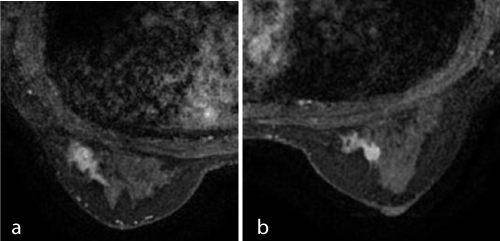

Case 3

2021 Copyright OAT. All rights reserv

a:      15-mm mass with irregular margin suggestive of IDCa.

b:      6-mm nodule. Breast cancer could not be excluded. Pathology: 5-mm IDCa.

Case 4

a:      25-mm mass with irregular margin.

b:      Stippled enhancements immediately behind the nipple are distributed in the upper area of the breast, suggestive of DCIS. Pathology: 50-mm IDCa.